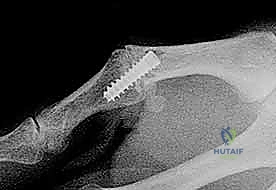

2. التصوير بالأشعة السينية (X-rays)

يُعد التصوير الشعاعي الخطوة الأولى لاستبعاد وجود كسور مصاحبة. في كثير من الأحيان، ينسلخ الرباط ويسحب معه قطعة صغيرة من العظم (Avulsion fracture). كما يتم أخذ صور أشعة تحت الإجهاد (Stress X-rays) لتوثيق عدم الاستقرار.